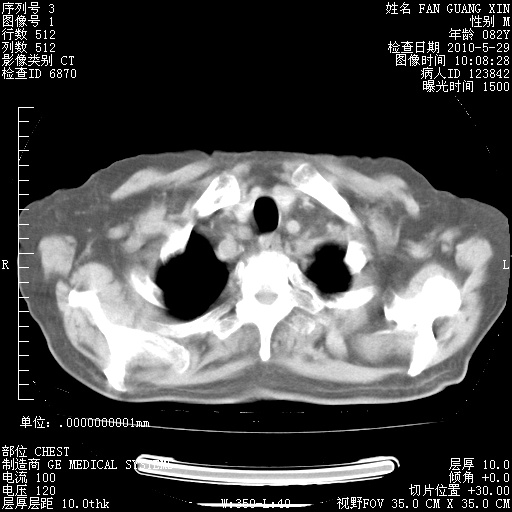

再治疗10天后的肺部CT